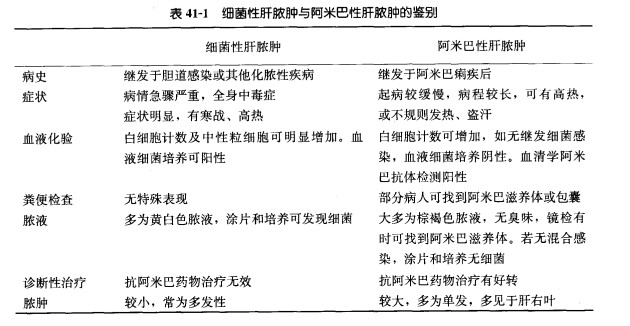

(一)阿米巴肝脓肿:这是细菌性肝脓肿的必须鉴别疾病。

(二)右膈下脓肿:发热,初为弛张热。脓肿形成以后持续高热.也可为中等程度的持续发热。脉率增快,舌苔厚腻。逐渐出现乏力、衰弱、盗汗、厌食、消瘦、白细胞计数升高、中性粒细胞比例增加。脓肿部位可有持续钝痛.深呼吸时加重。疼痛常位于近中线的肋缘下或剑突下。脓肿位于肝下靠后方可有肾区痛.有时可牵涉到肩、颈部。脓肿刺激膈肌可引起呃逆。膈下感染可通过淋巴引起胸膜、肺反应,出现胸水,咳嗽、胸痛。脓肿穿破到胸腔发生脓胸。近年由于大量应用抗生素,局部症状多不典型。严重时出现局部皮肤凹陷性水肿.皮肤温度升高。患侧胸部下方呼吸音减弱或消失。右膈下脓肿可使肝浊音界扩大。约有10%-25%的脓腔内含有气体。有时与细菌性肝脓肿不容易鉴别。B超检查或CT检查对右膈下脓肿的诊断及鉴别诊断帮助较大。